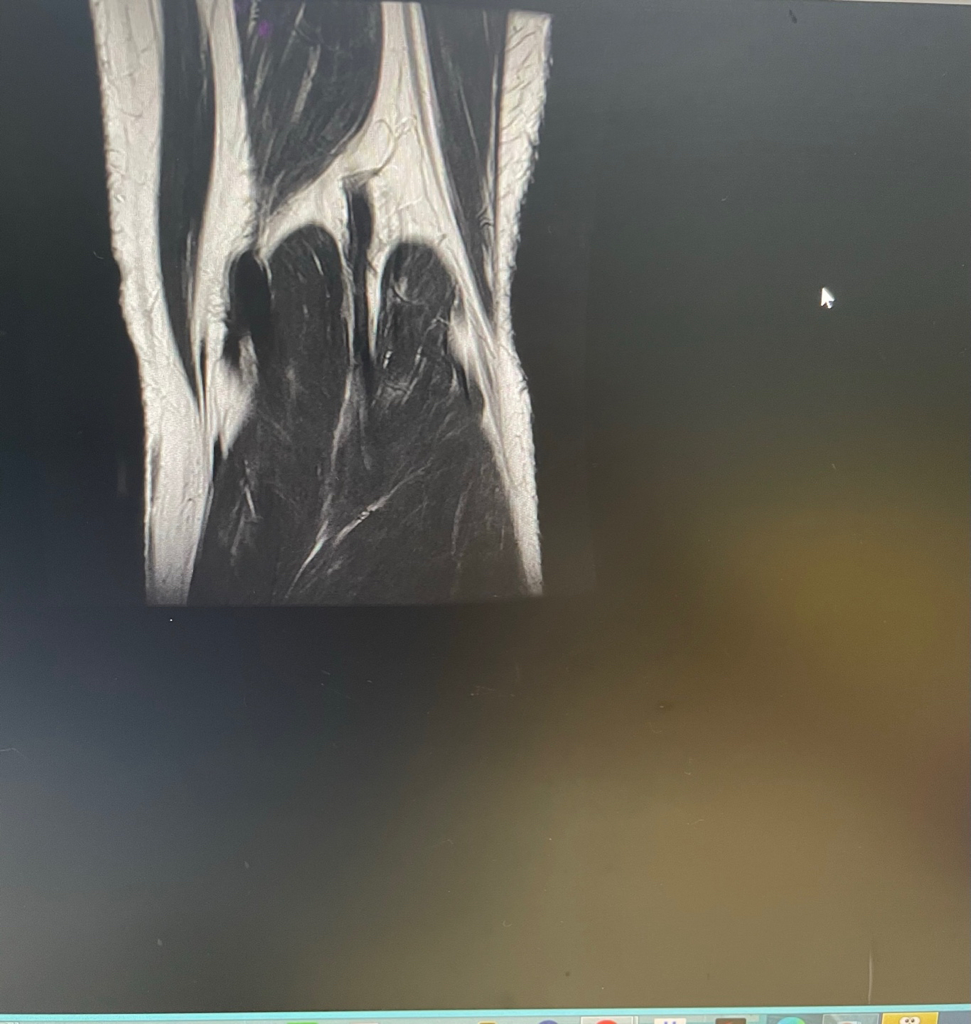

무릎이 너무 자주 아파서 mri를 찍어봤는데 무릎 연골에 이상이 있을까요

무릎이 선천적으로 원형연골인지 봐주시면 감사하겠습니다

• 4번 째 사진

MRI 판독에는 퇴행성 연골 손상, 바깥쪽 원판형 반월상 연골 이 의심된다고 적혀 있습니다.